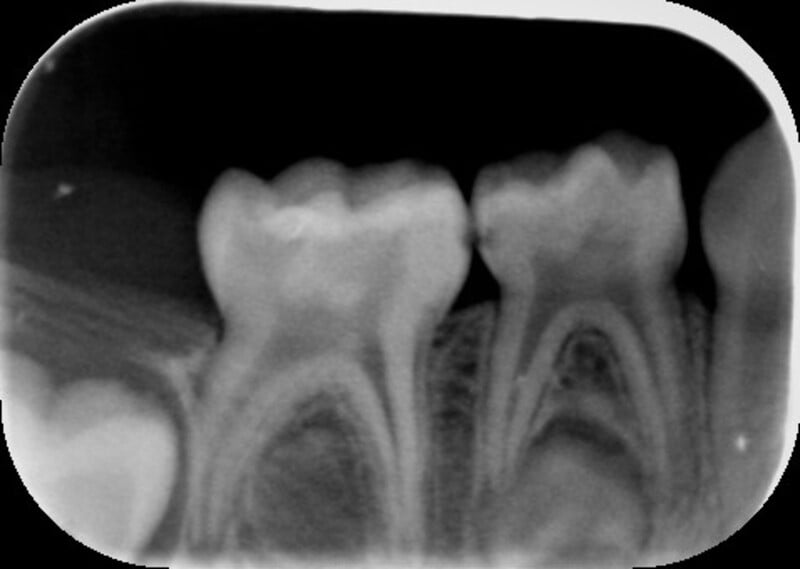

Foi realizado um exame clínico e radiológico inicial (fig. 1 a 3), tendo sido diagnosticada, entre outras lesões de cárie, uma lesão de cárie profunda com atingimento pulpar no segundo molar temporário inferior direito (fig. 3). Foi proposta a realização de uma pulpotomia com agregado trióxido mineral (MTA) e a colocação de uma coroa pré-formada. As várias possibilidades restauradoras foram apresentadas e discutidas com os pais, que decidiram optar pela colocação de uma coroa pré-formada de zircónia, por motivos estéticos.

No exame clínico e radiográfico realizado seis meses após o tratamento, não foi referido nenhum sintoma nem foram observados sinais indicadores de fracasso (fig. 10 e 11). Na radiografia periapical é possível observar a presença de pontes de dentina à entrada dos canais radiculares (fig. 11).

A utilização de MTA em pulpotomias de molares temporários apresenta uma elevadíssima taxa de sucesso observável no plano radiográfico pela ausência de imagens radiolúcidas na região apical e da furca radicular, e pela presença de pontes de dentina na entrada dos canais radiculares.7,8,9